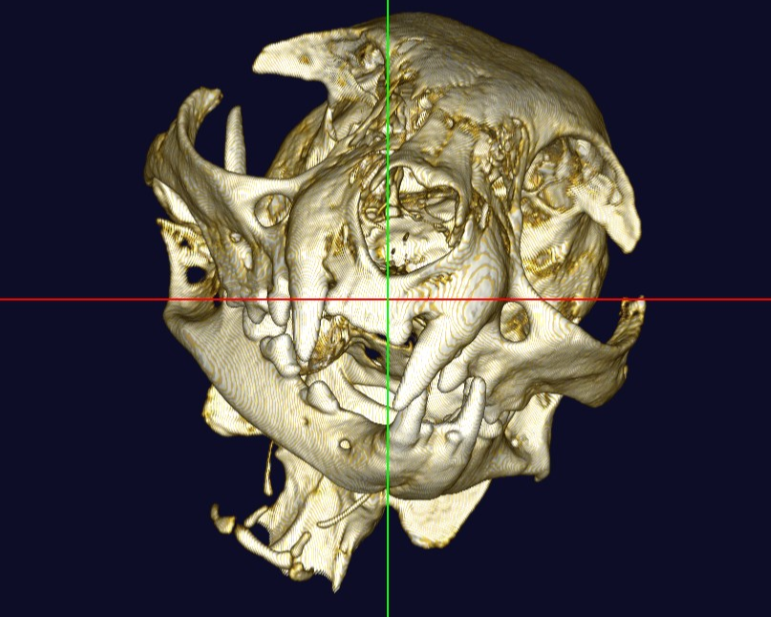

中・小型動物用3DマイクロCT

CTとはコンピューター断層撮影(Computed Tomography)の略で、X線を用いて身体の横断像(輪切り)を撮影することが出来ます。立体3D画像が得られるのも特徴で、主に骨格の異常や臓器系の異常部位、腫瘍性病変の把握に利用されます。

当院では「中・小型動物用3DマイクロCT」を導入しています。エキゾチックペットから猫・小型犬まで撮影可能です。

高画質で立体的に見ることで、レントゲンや超音波検査では分からない病態の診断や、構造が複雑な部位の細かい評価が可能です。

体の断層像に加え立体3D画像の作成が可能

事前に病変部位やその周囲の臓器との関係性を把握することで、より正確で安全な外科手術につながります。

また、飼い主様へお話しする際に、立体の3D画像のため病変のイメージがしやすくなります。

猫 頭部CT